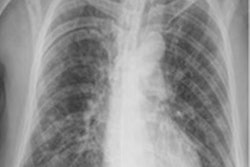

Technegas is a technology that enables ventilation scintigraphy with technetium-99m (Tc-99m)-labeled carbon nanoparticles (CNP). These nanoparticles are produced and aerosolized using on-site generators made by Cyclopharm subsidiary Cyclomedica, with patients inhaling the agent before undergoing lung imaging with a gamma camera.

Initially, Cyclopharm said it plans to target an estimated 600,000 Tc-99m-CNP nuclear medicine imaging procedures in the U.S. for pulmonary embolism.